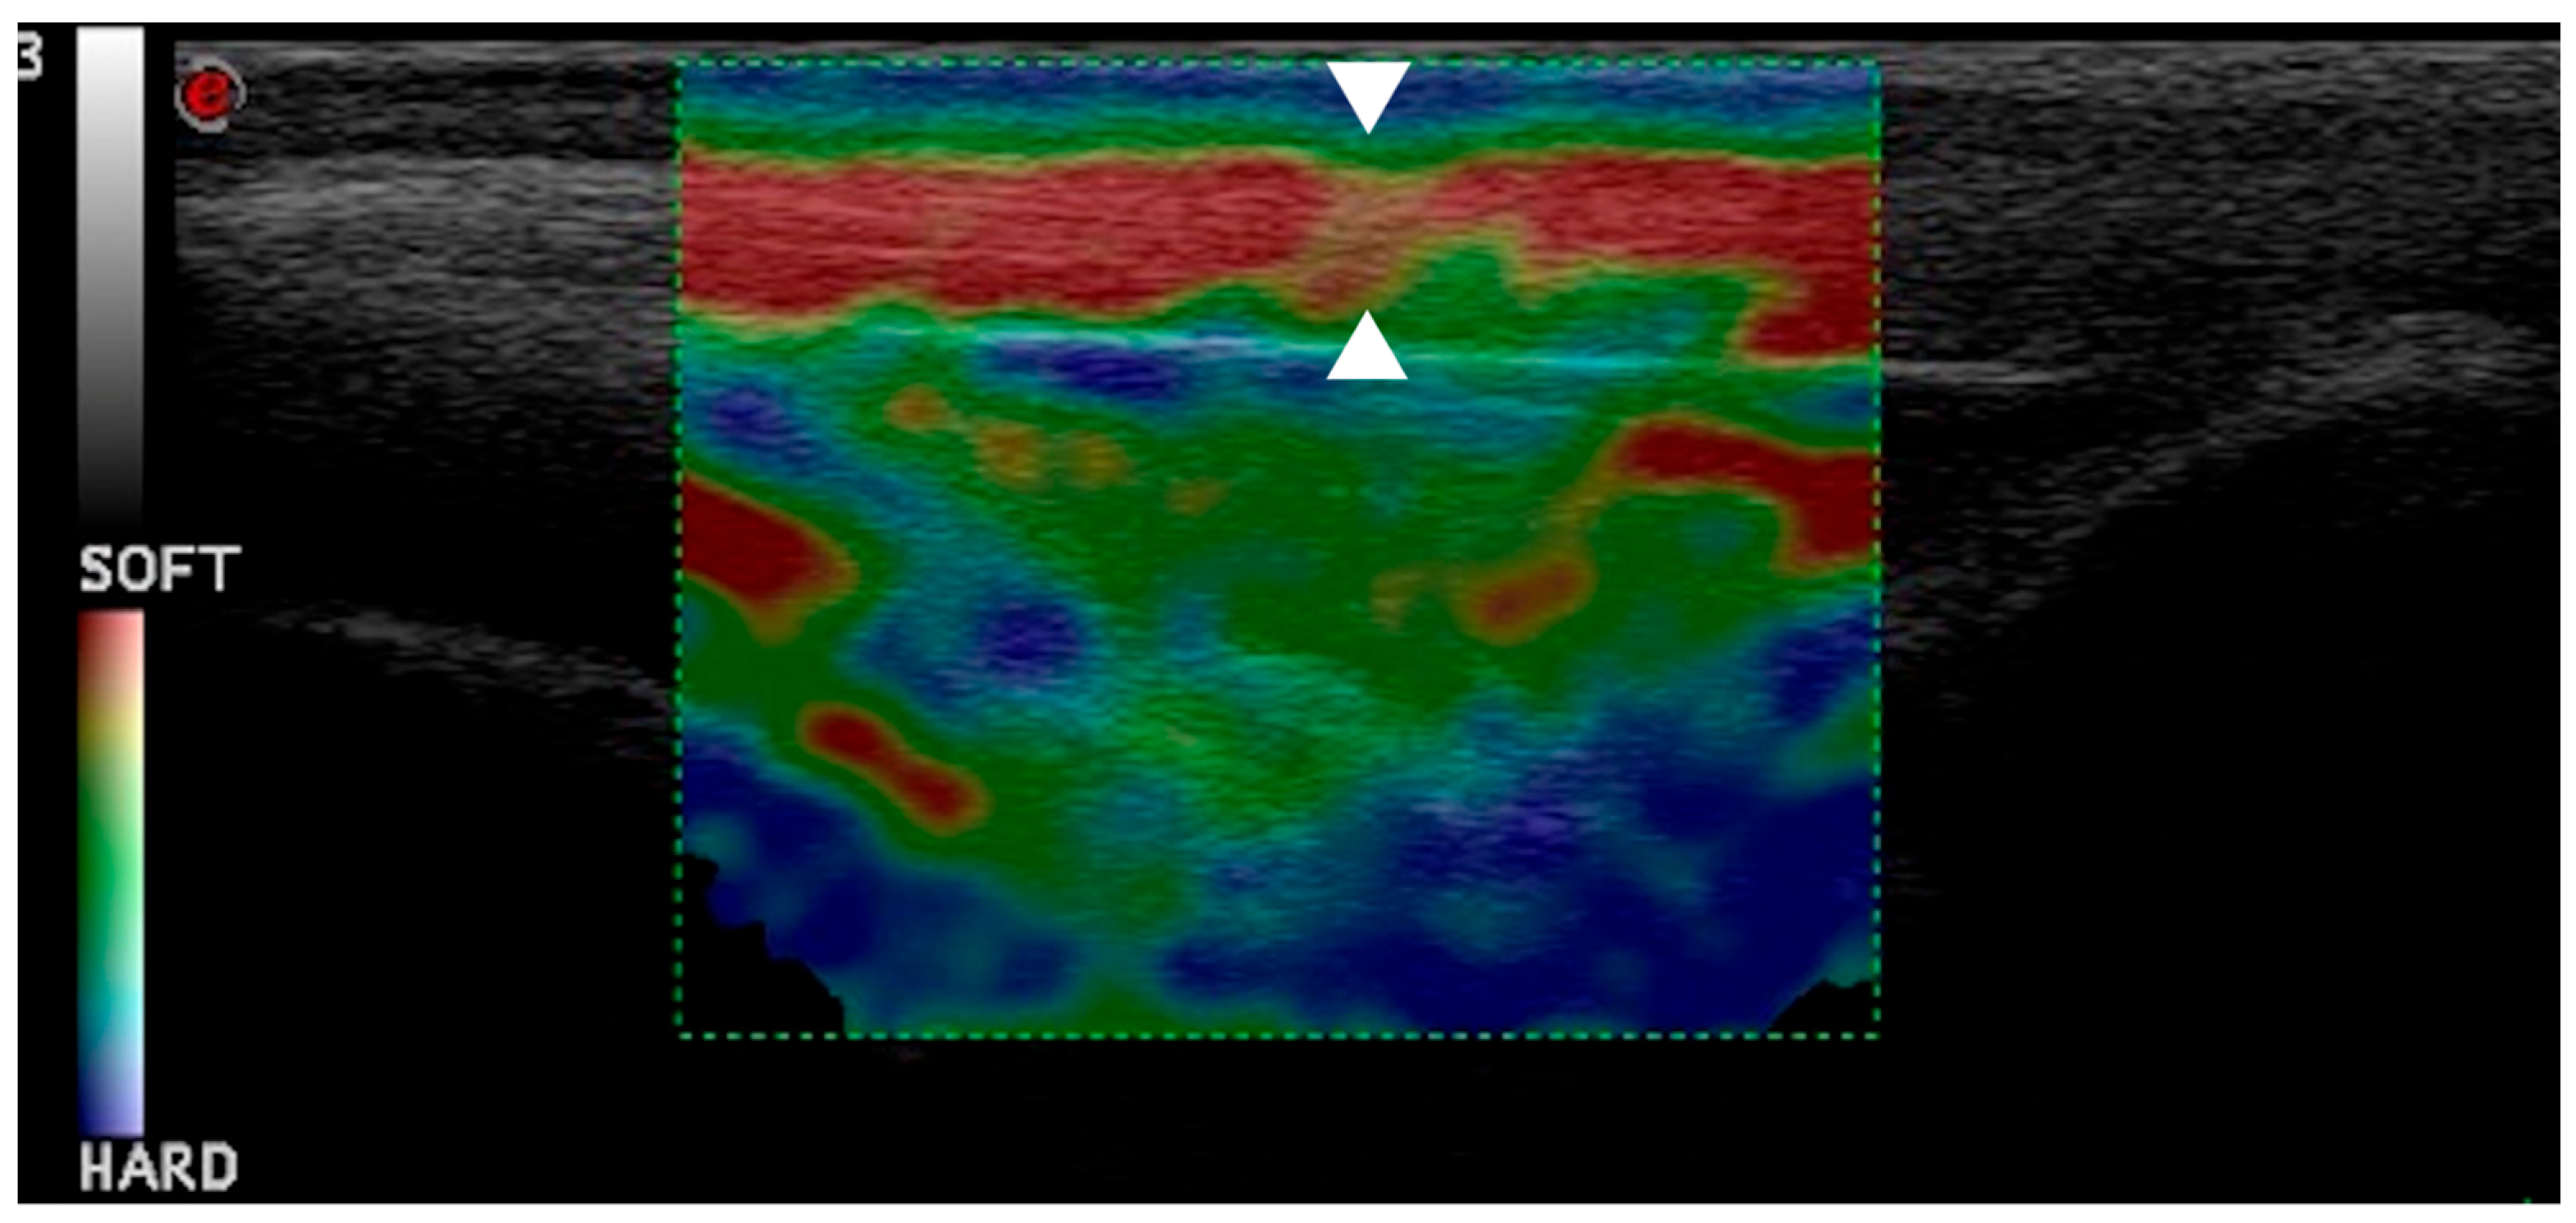

2.4. Ultrasonographic and Strain Elastosonographic Evaluations

3.3. Strain Elastosonographic Evaluation